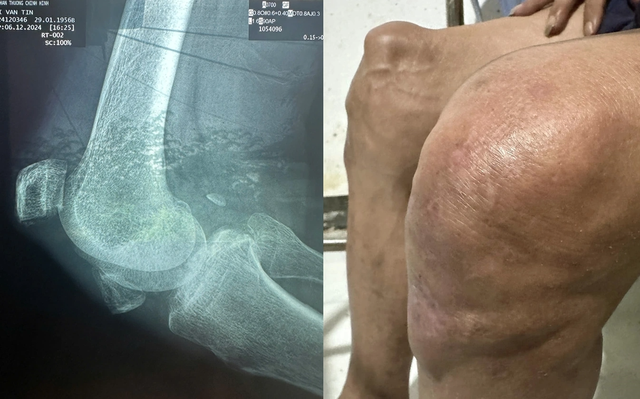

A imagem do joelho inchado da artista Thuong Tin devido à artrite e à patela quebrada comove muitas pessoas.

Antes do Tet (Ano Novo Lunar), o artista foi levado por sua família à cidade de Ho Chi Minh para um exame médico no Hospital de Ortopedia e Traumatologia. Lá, o médico diagnosticou que Thuong Tin tinha um problema sério na perna e estava com a saúde debilitada. Especificamente, o ator tinha osteoartrite no joelho direito e uma fratura na patela direita.